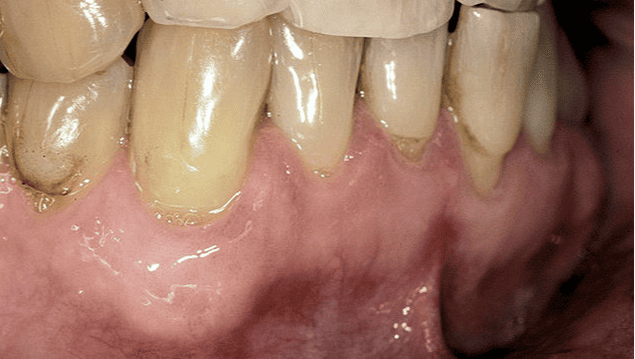

After treatment After